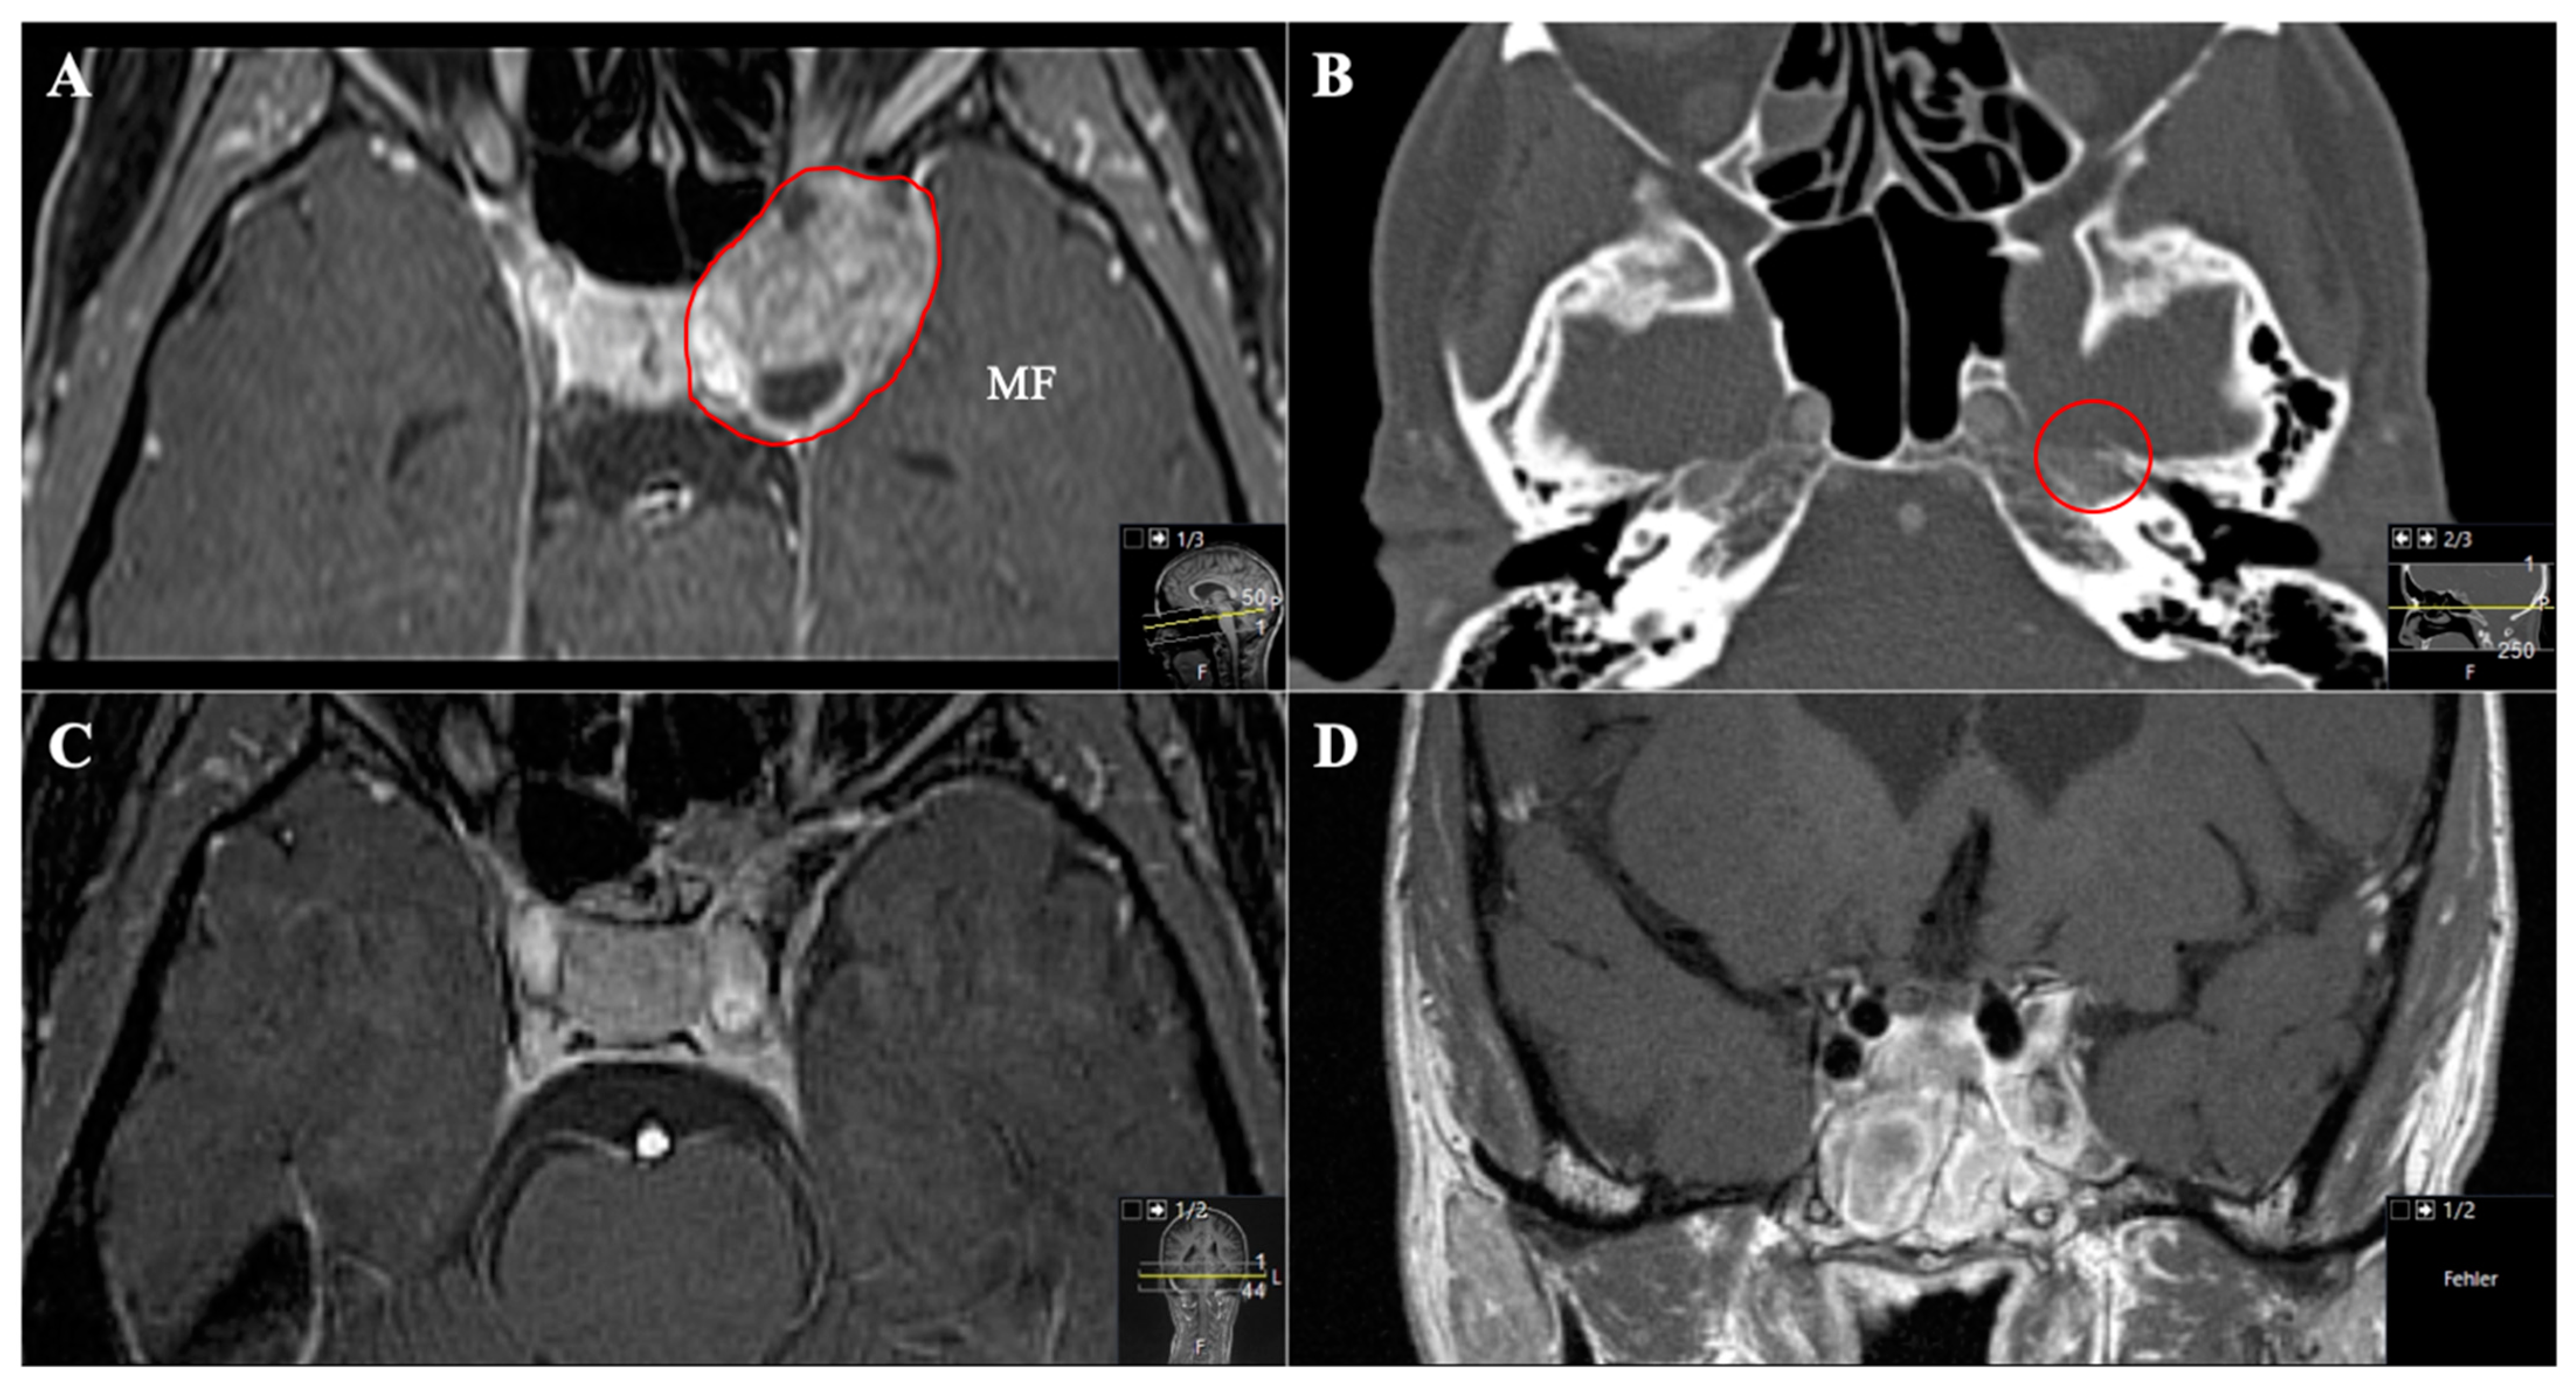

Figure 7. A 45-year-old female patient presented with left-sided visual impairment and headache. (A) Preoperative axial T1-weighted gadolinium-enhanced MRI and (B) axial CT, showing an optic-canal-compressing trigeminal schwannoma with a cystic part in Meckel’s cave in the middle fossa (MF, Samii Type A). Note how the foramen rotundum is widened (red circle). (C) Postoperative axial and (D) coronal MRI control, indicating complete resection via a transnasal endoscopic (transpterygoid) approach using a nasoseptal flap.